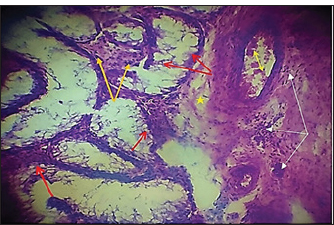

Histopathological evaluationThe zinc gluconate groupIn the GI group, 30 days post-injection, the testes section showed atrophy of the tubuli recti with dilatation of others, desquamation of the tubuli recti epithelium, infiltration of inflammatory cells, and degeneration of seminiferous tubules (Fig. 4). Fibroblast proliferation was observed around the thickened walls of blood vessels (Fig. 5). Other sections showed complete seminiferous tubule stroma necrosis with necrosis in tunica albuginea (Fig. 6). Despite the presence of Leydig cell clusters, some sections displayed germinal cell exfoliation in the lumen of seminiferous tubules accompanied by edematous interstitial tissue and inflammatory cell infiltration (Fig. 7).

Fig. 6. Histopathological section of testes from a dog of the zinc gluconate group at 30 days post-intrasticular injection, showing complete necrosis of seminiferous tubules (red stars) and stroma (black arrow), with necrosis in tunica albuginea(red dotted arrow)(H & E stain 10X).

Fig. 7. Histopathological section of testes from a dog in the zinc gluconate group at 30 days post-intrasticular injection, showing exfoliation of germ cells (red arrows), infiltration of inflammatory cells (white arrows), Leydig cell clusters (yellow arrow), edema (star), and congestion (yellow head arrow) (H & E stain 10X). Surgical groupIn the surgical group (GII), the main characteristic findings at 30 days post-surgery were degeneration of seminiferous tubules, multinucleated spermatid, infiltration of inflammatory cells, atrophy of Leydig cells, and vacuole degeneration of basal and Sertoli epithelium (Fig. 8). Furthermore, there was loss of the straight shape of the tubuli recti, disequimentaion of the tubuli recti epithelium, and proliferation of myoid cells (Fig. 9). Other sections showed coagulative necrosis and ghost tubules in the rete testis (Figs. 10 and 11).